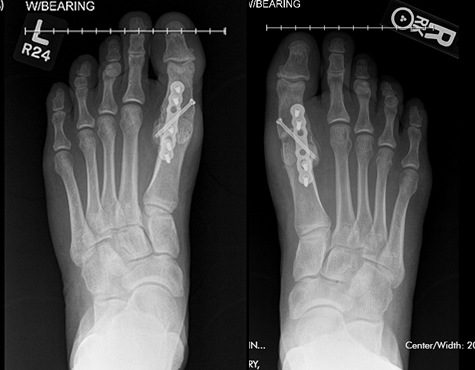

I suffered from Hallux Rigidus of the left metatarsaloflangeal joint, or, a really sore big toe, big joint. I had developed a slow but deliberate pain in my toe and had suffered with it for a few years before seeking a specialist's opinion. My primary care physician was convinced that it was an early bunion. He sent me to a local surgeon who performed a "scrape and flush "procedure on the bone spurs and gunk that had developed in the joint. It didn't help. They recommended trying a cortisone injection; only made it worse.

Dr. Leavitt recommended fusing the joint that had been ravaged by an active life and arthritis.

Two years later, in 2016, the pain in my other big toe had grown to the point that I knew what was going on. I wasn't going to put it off like I had on my left foot. Dr. Leavitt was again amazing, even making sure that my scars would match. This time Dr. Leavitt took my previous compliance as a good patient (please do as he says) into consideration and made some accomodations to my casting so I would have less muscle wasting. Just like last time, my recovery went well and on time. In a word: Incredible.

The diagnostic radiographs (X-rays) prior to the first surgery, did not indicate the extent of the actual pathology. This is sometimes the case, but thanks to extensive past experience, I was able to recognize the problem for what it was. Once inside the foot, we found that half the cartilage was gone. That wouldn't always show on the x-ray.